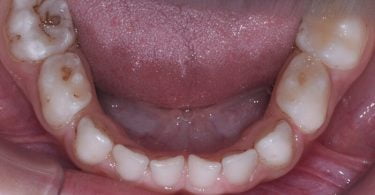

Foi realizado um exame clínico e radiológico inicial (fig. 1 a 3), tendo sido diagnosticada, entre outras lesões de cárie, uma lesão de cárie profunda com atingimento pulpar no segundo molar temporário inferior direito (fig. 3). Foi proposta a realização de uma pulpotomia com agregado trióxido mineral (MTA) e a colocação de uma coroa pré-formada. As várias possibilidades restauradoras foram apresentadas e discutidas com os pais, que decidiram optar pela colocação de uma coroa pré-formada de zircónia, por motivos estéticos.